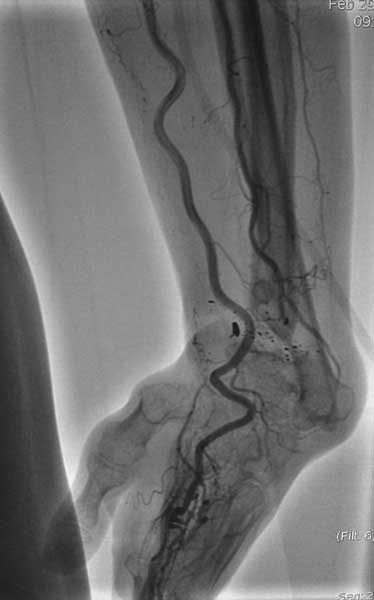

Изучали ли вы достаточно тщательно ангиограммы пораженного сегмента? Если да, то вы обратили внимание, что в артериальной фазе практически полностью отсутствует контрастирование лучевой артерии в зоне дефекта, тем самым вы имеете разорванную артериальную дугу и стабильный кровоток только в одном бассейне-локтевой артерии, тыльная межкостная не контрастировалась. Невзирая на это, вы предлагаете использовать пластику дефекта трансплантатом локтевой кости на сосудистом пучке (единственном, который объективно сохранился). Не боитесь ли вы возникновения проблем кровоснабжения кисти при выполнении данного вмешательства и как вы готовы бороться с этим (имею в виду оснащение, специалистов по микрохирургии и пр.)-это вопрос номер 2.